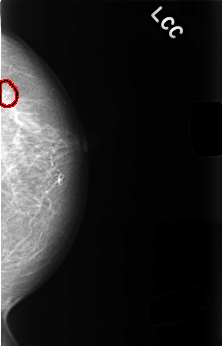

C_0476_1.LEFT_CC

LEFT_CC LINES 4496 PIXELS_PER_LINE 2880 BITS_PER_PIXEL 12 RESOLUTION 50 OVERLAY

FILE: C_0476_1.LEFT_CC.OVERLAY

TOTAL_ABNORMALITIES 1

ABNORMALITY 1

LESION_TYPE CALCIFICATION TYPE PLEOMORPHIC DISTRIBUTION CLUSTERED

ASSESSMENT 4

SUBTLETY 4

PATHOLOGY BENIGN

TOTAL_OUTLINES 1

BOUNDARY